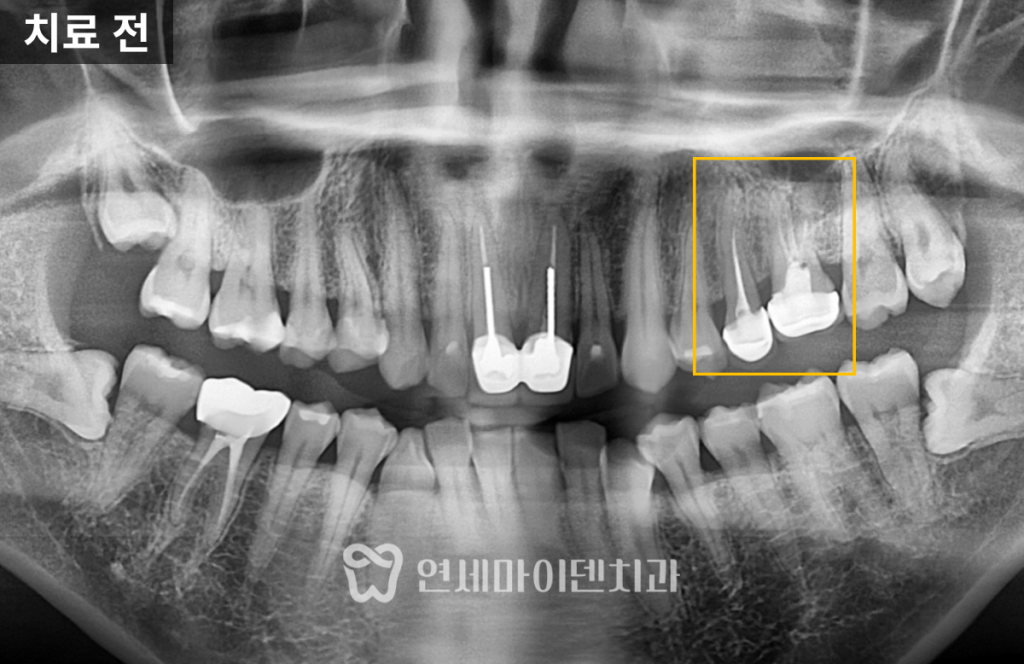

환자 증상과 진단 과정

환자분은 “왼쪽 위 어금니가

시리고 아프다”고 호소하셨습니다.

#25번과 #26번 두 치아 모두 과거

신경치료를 받은 상태였으며,

염증이 관찰되었습니다.

환자분의 덴탈 히스토리(치료 시기, 통증 시점, 악화 요인 등)를 자세히 확인하고,

파노라마와 CT를 함께 분석하여 정확한 원인을 찾았습니다.